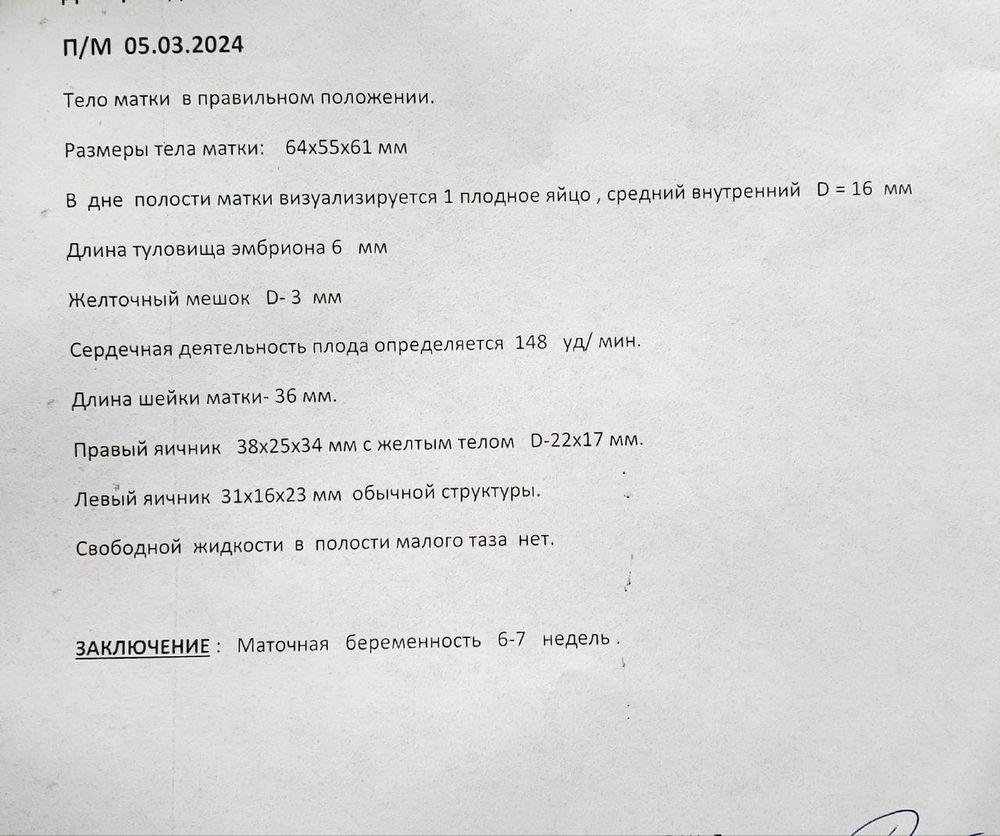

Учитывая, что у меня последние М были 05.03, а овуляция поздняя на 22 ДЦ, то думаю срок 6-7 недель соответсвует. По М у меня срок 7+3, если считать от О назад 14 дней, то 6+3. По узи сказали полных 6 недель, написали 6-7 недель.

Длина туловища эмбриона - это я так понимаю ктр, смешно написали))

Наиля , дааа, при чем не смотря на позднюю овуляции, практически по сроку не отстает. Сначала немного парилась из-за размера СВД , что он 16 мм, а эмбриончик аж 6 мм. но и врач и узист сказали, что всё хорошо